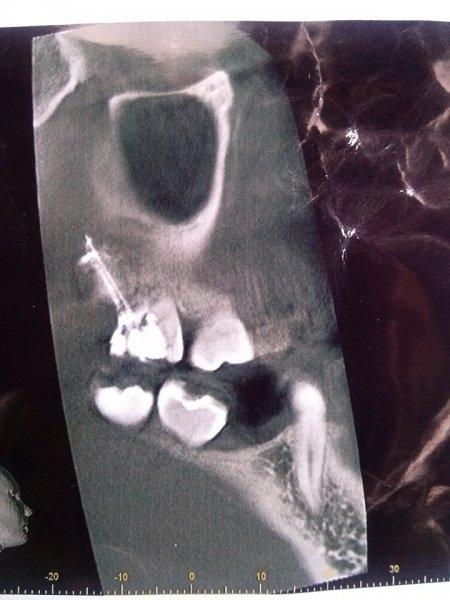

Після довгих дискусій лікар таки дала Іванці направлення на рентген. Коли дівчині зробили знімок, вона там помітила дивну білу пляму, схожу на спіраль. Однак Тетяна Миколаївна запевнила, що «це нічого». Медик знову поставила тимчасову пломбу на кілька днів.

Однак в Іванки закралися сумніви. Вона вирішила звернутися до іншого лікаря, але вже в клініці центру стоматології ІФНМУ. Стоматолог Оксана Волосовська відразу спрямувала дівчину на томографію. Зрештою здогади медика підтвердилися – у кістці та в коронці зуба застряг інструмент для пломбування каналу, який має вигляд спіралеподібної залізної голки завдовжки близько 3 см.